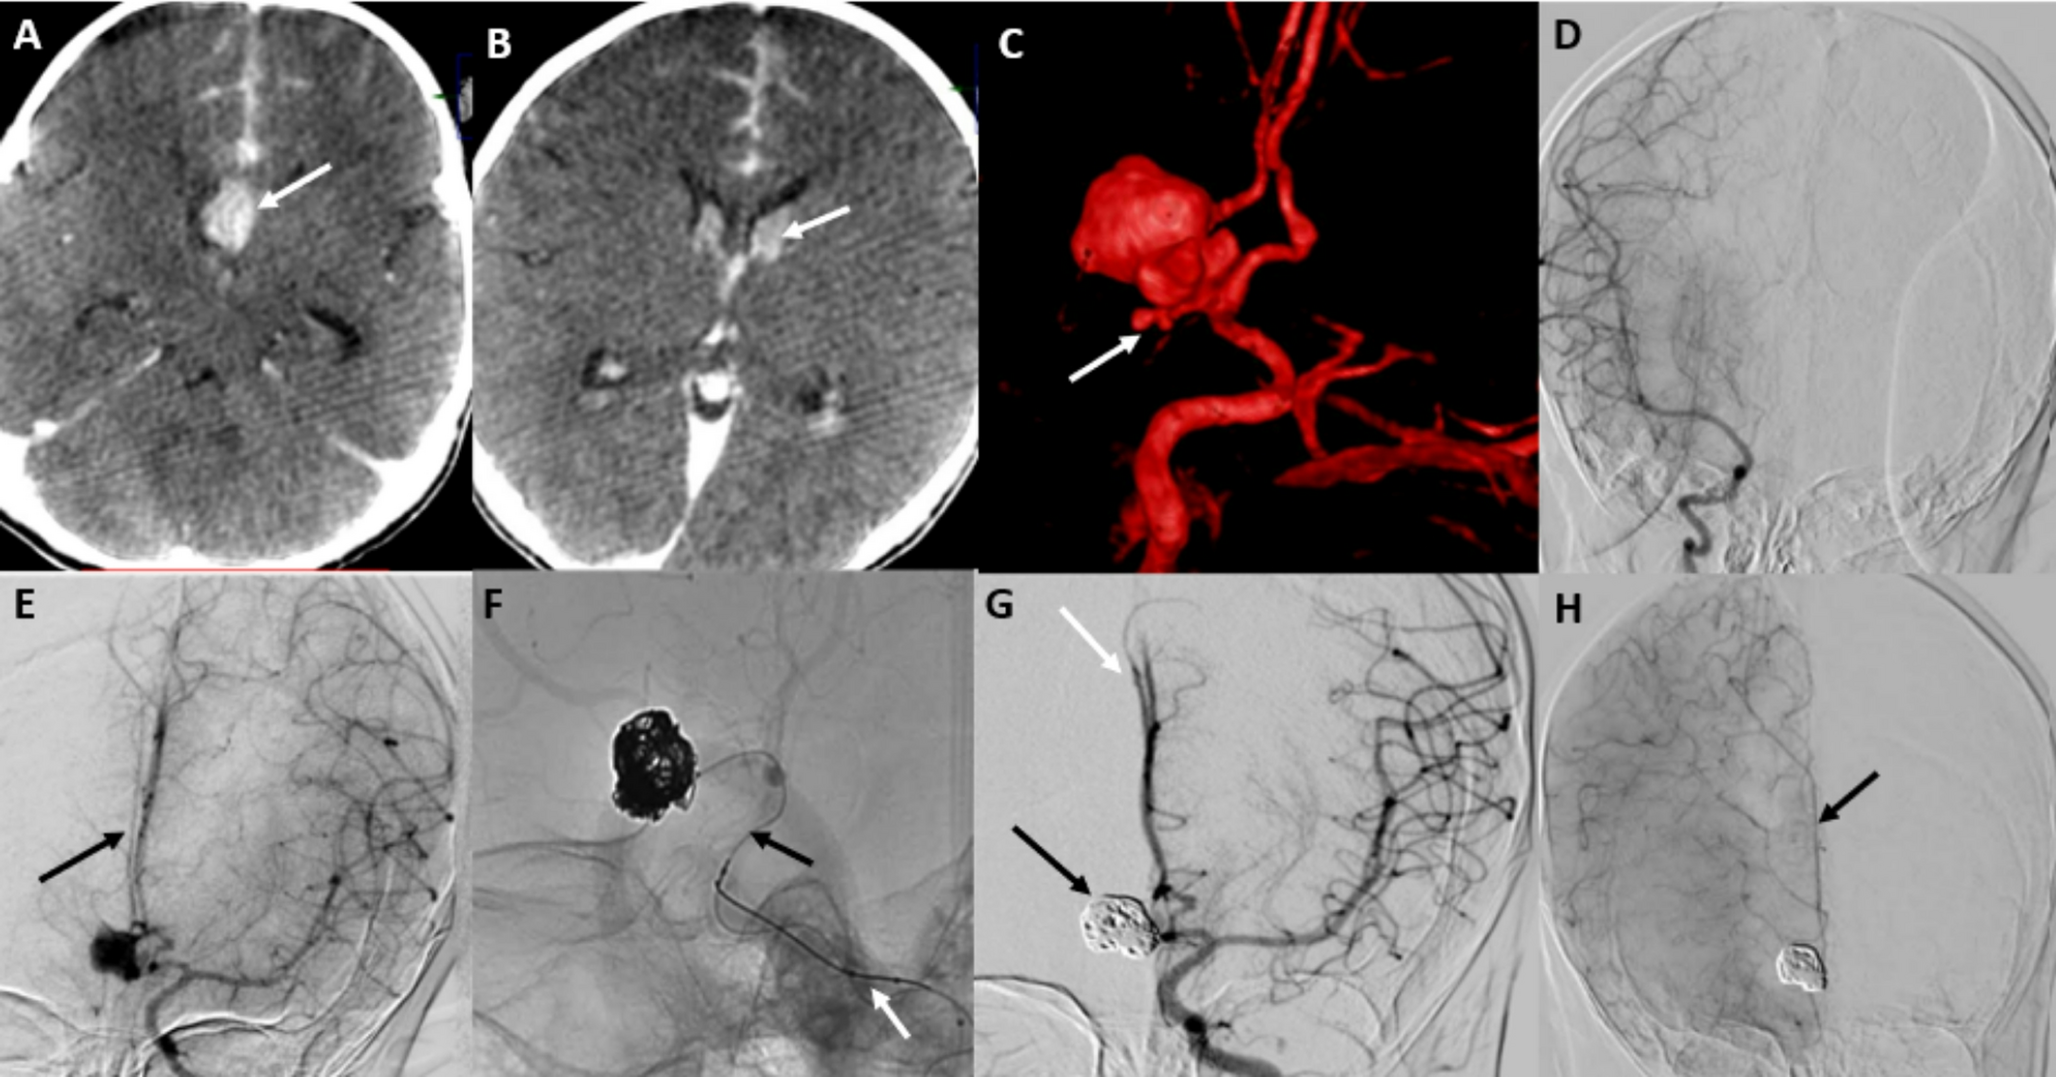

Endovascular management of a ruptured complex ACoM aneurysm in a 9-month-old infant: a rare case report and literature review

Ruptured intracranial aneurysms in infants are exceptionally rare, particularly saccular aneurysms of the anterior communi...